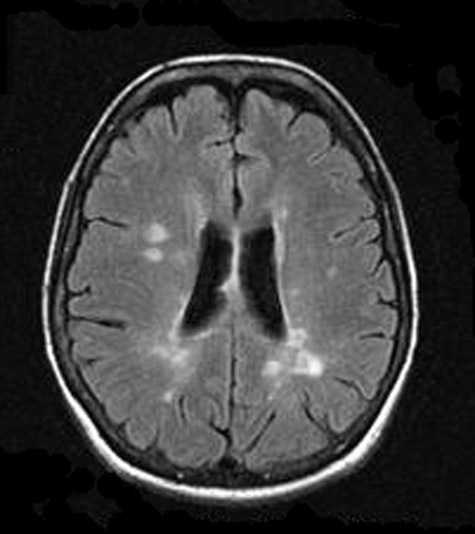

Томограмма мозга пациента с рассеянным склерозом. Видны множественные очаги поражения в ткани мозга.